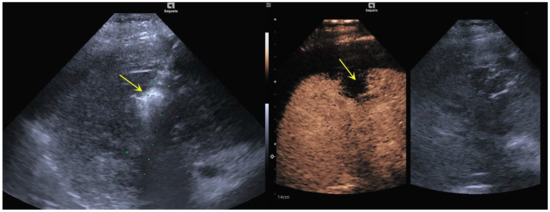

3.1. Imaging Features